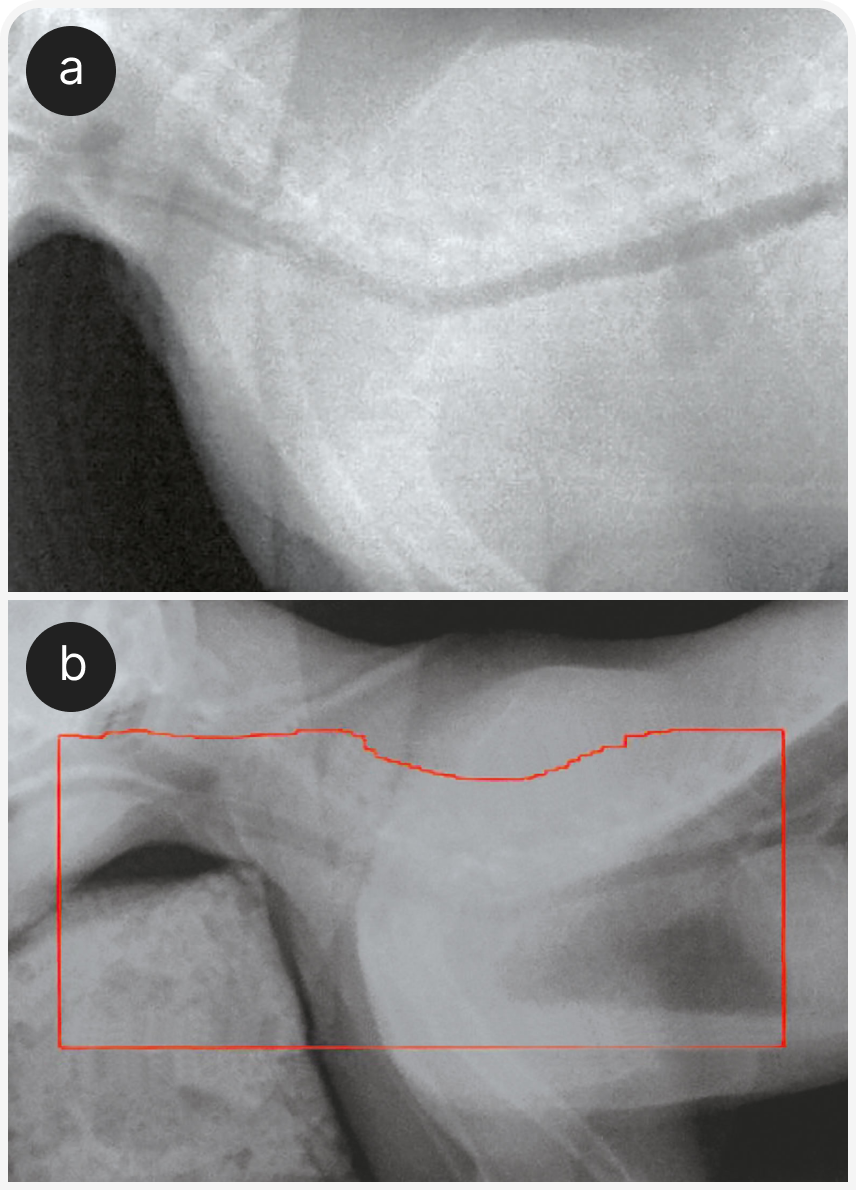

Для установления диагноза может быть достаточно цитологического исследования тонкоигольного аспирата (FNA) образования или плевральной жидкости. У большинства кошек лимфома легко отделяется при тонкоигольной аспирации; диагноз подтверждают при обнаружении мономорфной популяции промежуточных или крупных лимфоидных клеток (Рисунок 4). В некоторых случаях окончательная диагностика лимфомы у кошек с объемным образованием в средостении может оказаться более сложной.

Основной дифференциальный диагноз для лимфомы средостения — тимома. Цитологически тимому во многих случаях можно отличить от лимфомы, но диагностику может осложнять преобладание в тимоме малых лимфоцитов. Тучные клетки также визуализируют в 50% аспиратов из тимомы (Рисунок 5). В неоднозначных случаях может оказаться полезным дополнительно оценить иммунофенотипические показатели и клональность.